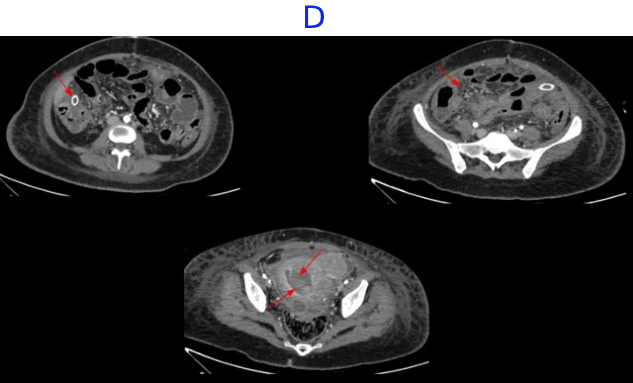

• D. Bulky uterus with a hypodense submucosal lesion protruding into the endometrial cavity from the fundus showing heterogeneous enhancement - infected vs infarcted fibroid. Abnormally enhancing endometrial lining with hypodense content within the endometrial cavity - possible endometritis with pyometra. Pelvic peritonitis with residual trace fluid in the pelvis. Interval resolution of pneumoperitoneum. Abdominal drains in situ.

• Bulky uterus with a hypodense submucosal lesion protruding into the endometrial cavity from the fundus showing heterogeneous enhancement - infected vs infarcted fibroid.

• Abnormally enhancing endometrial lining with hypodense content within the endometrial cavity - possible endometritis with pyometra

• Left sided hydro/pyosalpinx.